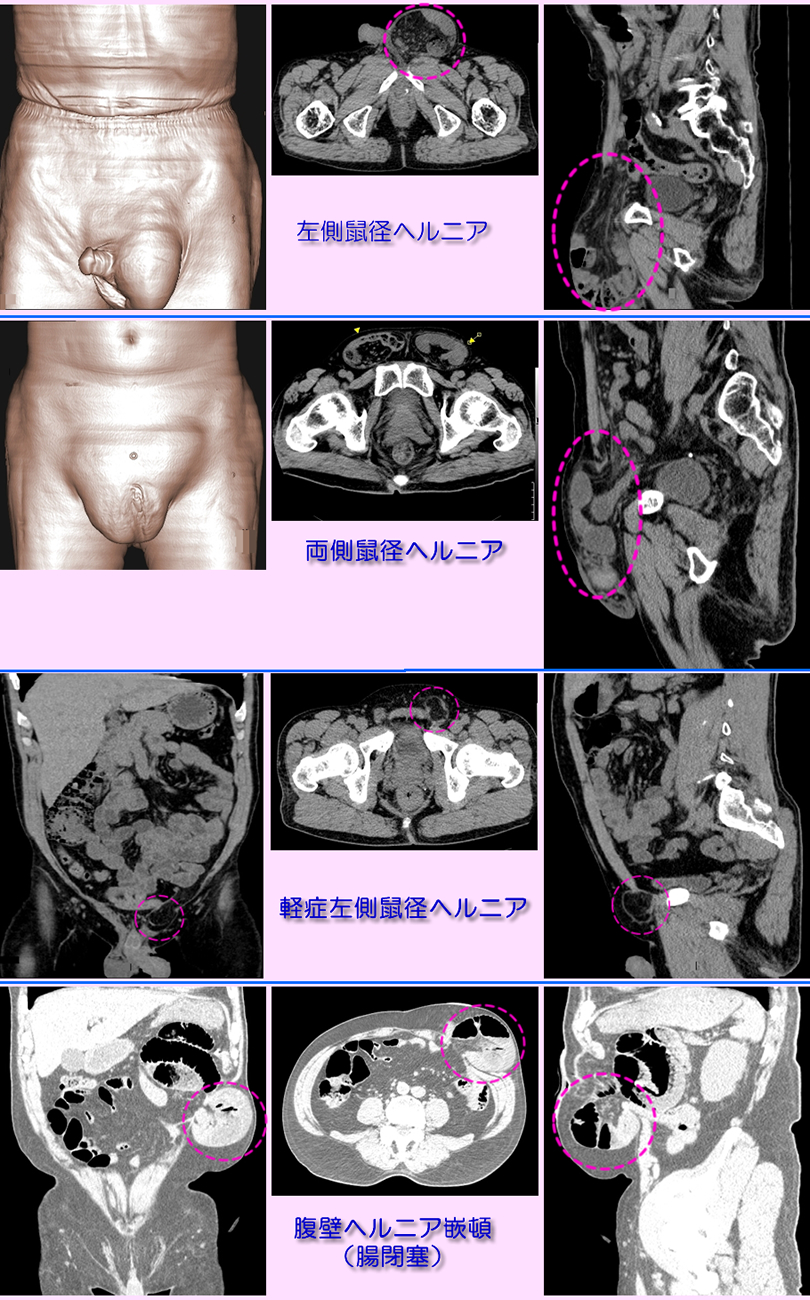

ヘルニア(鼠径・腹壁)

ヘルニアの部位により鼠径部、陰嚢部、大腿部の膨隆、腹壁ヘルニアは 手術部位の腹壁が薄くなり、腸管が薄く膨隆した腹壁部位に入り込む。CTは膨隆部の内容物(腸管)の確認や範囲(重度)の評価に有用。下段にヘルニアのMDCT検査画像を提示します。